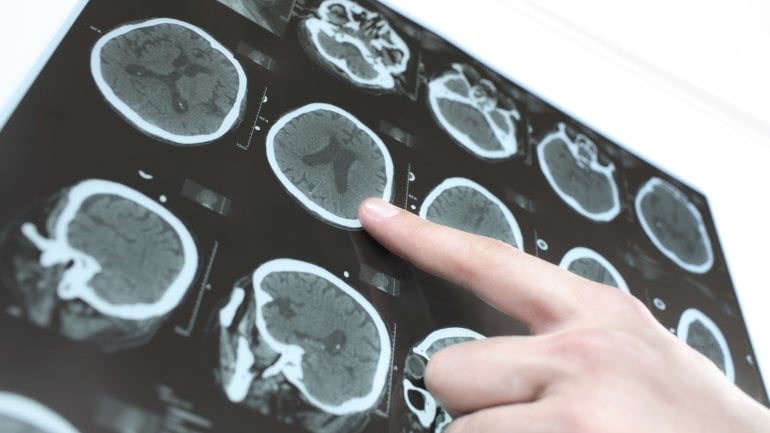

Bestätigen diese Tests den Verdacht einer Subarachnoidalblutung, fertigt der Arzt so rasch wie möglich CT-Aufnahmen von Schädel und Gehirn an (craniale Computertomographie, CCT). Hier ist die Blutung meist deutlich zu erkennen.